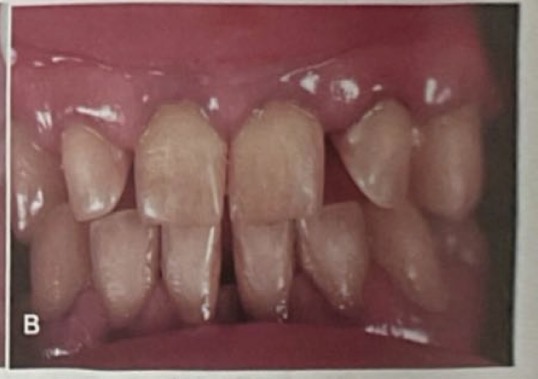

CHẨN ĐOÁN ?

SÂU RĂNG SAU XẠ TRỊ( sâu nhiều răng và lang quanh cổ răng)